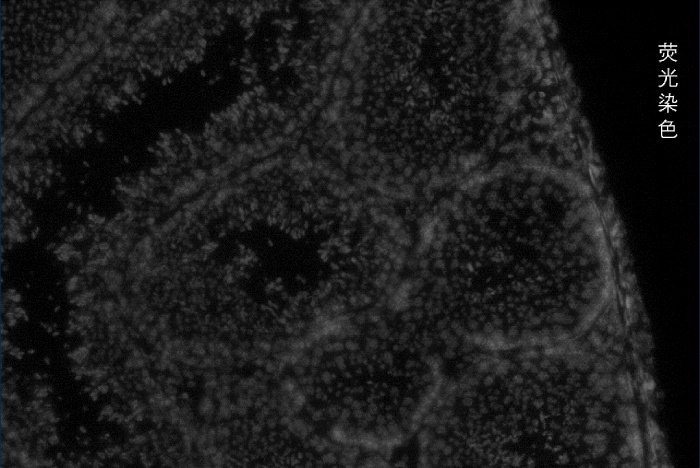

百創(chuàng)智造于2022年4月25日推出了4.8μm分辨率空間轉錄芯片百創(chuàng)S1000以來,受到了市場的廣泛好評與認可。經過又一年的研發(fā)沉淀,2023年6月28日,百創(chuàng)智造將技術回歸生命科學本質,開創(chuàng)性的將樣本原片熒光、原片H&E染色與原片高通量測序相結合,)在山東青島正式舉辦了百創(chuàng)智造S系列空間轉錄組細胞分割產品發(fā)布會。會上正式發(fā)布了基于百創(chuàng)S系列空間芯片的細胞分割技術,重新定義空間組學新標準,開啟單細胞級空間轉錄組科研時代。

百創(chuàng)智造基于S系列空間芯片的底層設計,可以得到完全沒有錯誤的原片熒光圖像以及H&E圖像且與芯片完全對齊?;跓晒膺M行細胞核的定位刻畫細胞核的邊界;基于HE的校準輔助刻畫細胞的邊界,通過邊界信息映射到芯片上,提取相應位置的測序數(shù)據(jù),實現(xiàn)精準的單細胞分割。